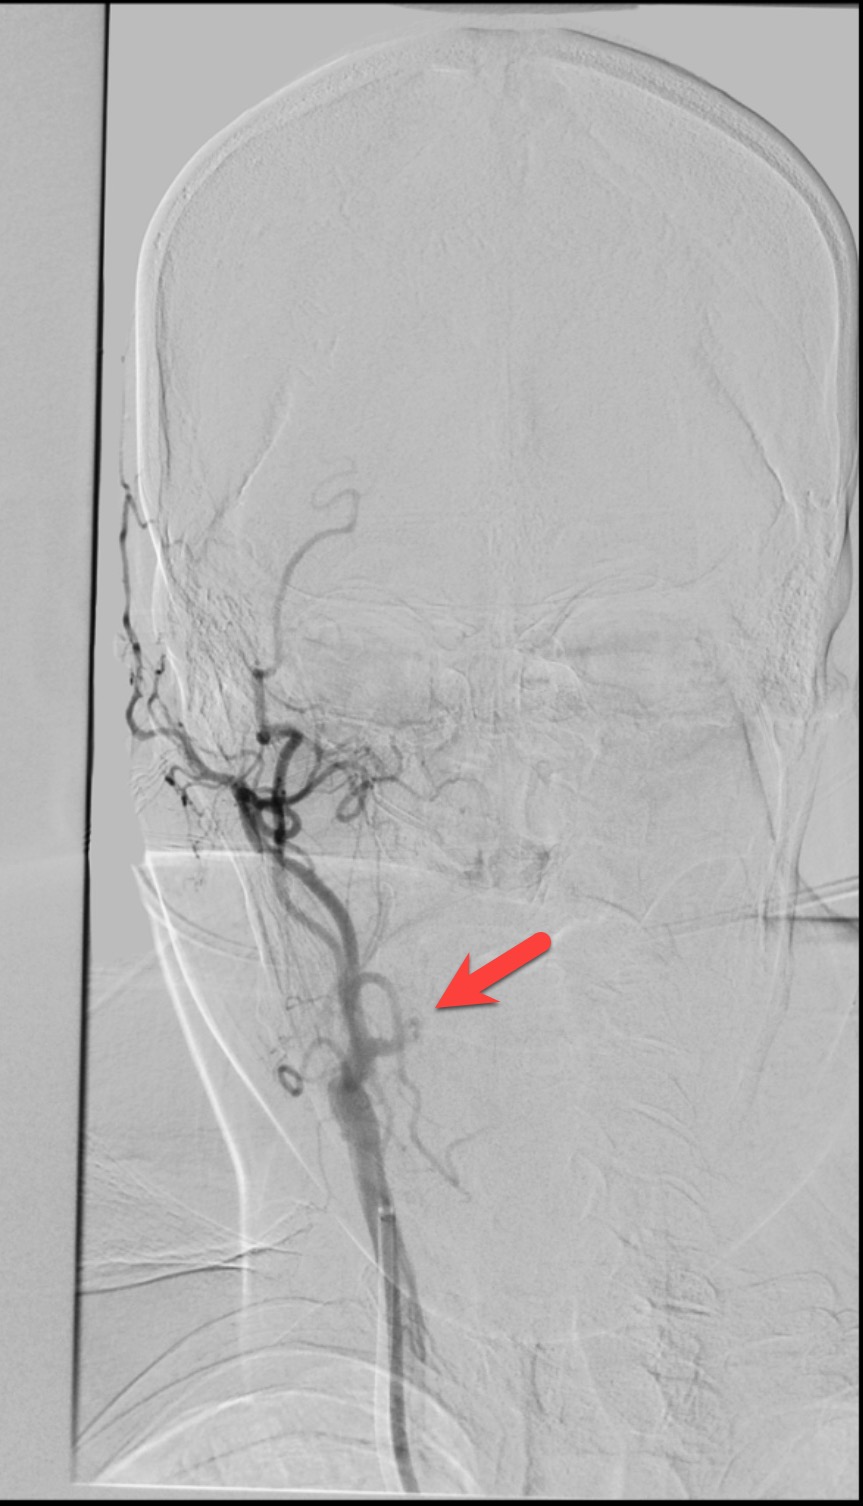

血管介入科医生凭借精湛的技术和丰富的经验,成功地完成了通过颈内动脉闭塞段、颈内动脉血栓抽吸、大脑中动脉取栓支架就位、取出大脑中动脉血栓、植入颈内动脉支架等一系列操作,成功地开通了血管,恢复了颅内的血流。经过血管介入科医生及护士的细心照顾,患者最终恢复了健康,没有残留明显的明显的后遗症。

右侧颈内动脉及大脑中动脉恢复通畅